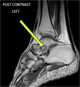

Sinus tarsi syndrome